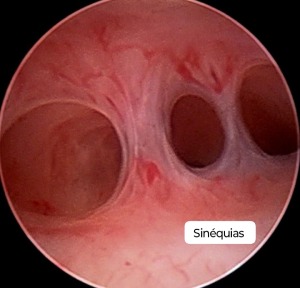

Lise de Sinéquias

Procedimento para remover aderências intrauterinas (sinéquias) usando a histeroscopia, que podem causar infertilidade ou problemas menstruais.